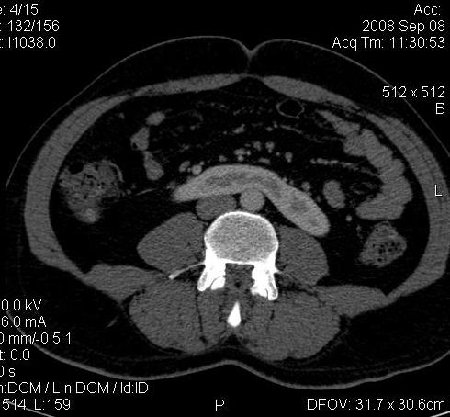

КТ Почек- подкова и уретеролитиаз

Данное наблюдение весьма демонстративно само по себе.

Ну ладно, раз никто больше не хочет, то отвечу свою версию - аномалия развития - подковообразная почка (horseshoe kidney).

Почечная колика; на последнем аксиальном скане чётко виден мелкий (2 мм) камень в устье правого мочеточника.

Для невладеющего КТ,очень четка видна аномалия на 3-4х снимках.А вот на 4-м скане в проксим.сегменте цистоида тоже есть гиперденсное точечное образование-не камень случайно?